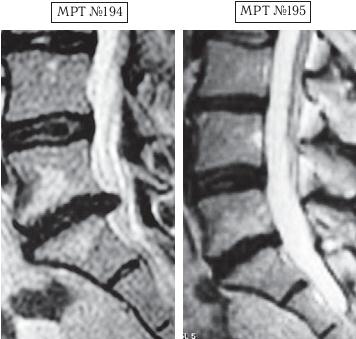

На МРТ № 198 наблюдается состояние поясничного отдела позвоночника: секвестрированная грыжа межпозвонкового диска в сегменте LV—SI абсолютный стеноз спинномозгового канала. На МРТ №199 — состояние поясничного отдела позвоночника после лечения методом вертеброревитологии. Пример № 5.